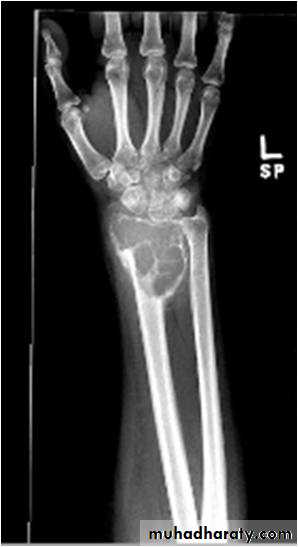

Subperiosteal bone resorption seen particularly in the radial aspect of the middle phalange (hyper parathyriodism)

Sub periosteal resorption at the radial aspect of the middle phalanges (hyper parathyriodism )